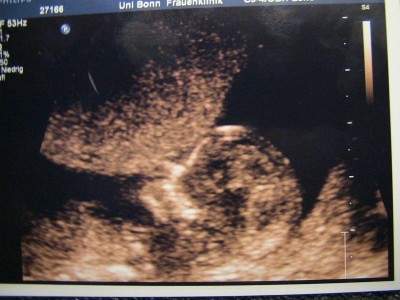

@Jaqueline: Wie süüüüüüüüüüüss!! So ein kleines Würmchen!!!

@Jaqueline: Herzlichen Glückwunsch zum Sohnemann!!!!! Jetzt schon lässig euer Kleiner, im Schneidersitz mit den Füssen winkend!!!

@Jaqueline: Herzlichen Glückwunsch zum Sohnemann!!!!! Jetzt schon lässig euer Kleiner, im Schneidersitz mit den Füssen winkend!!!COOL!!!!